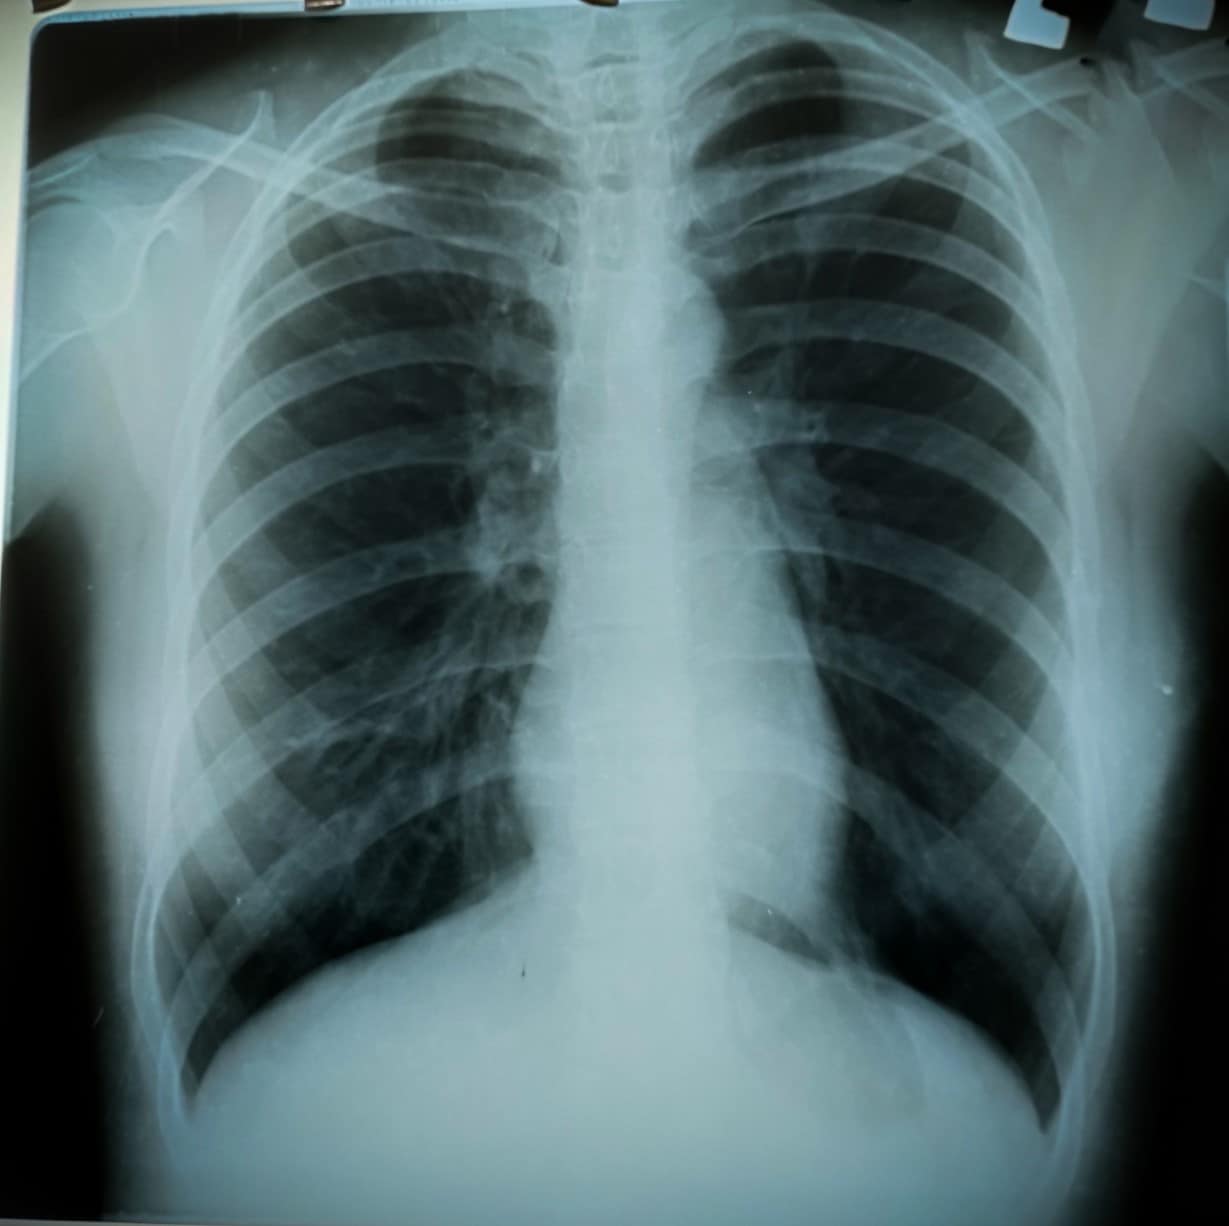

Clinical Pearl | Oct 24, 2024

Clinical Pearl: Workup of Left-Sided Chest Pain in a COPD Patient

A 69-year-old female presents to the emergency room (ER) with a 20-day history of left-sided sharp chest pain radiating to...Read More